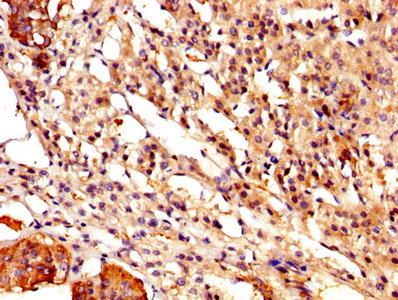

IHC image of CSB-PA004561YA01HU diluted at 1:500 and staining in paraffin-embedded human adrenal gland tissue performed on a Leica BondTM system. After dewaxing and hydration, antigen retrieval was mediated by high pressure in a citrate buffer (pH 6.0). Section was blocked with 10% normal goat serum 30min at RT. Then primary antibody (1% BSA) was incubated at 4°C overnight. The primary is detected by a biotinylated secondary antibody and visualized using an HRP conjugated SP system.